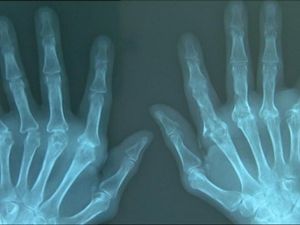

Pangeran Brunei Darussalam, Haji Abdul Azim, meninggal dunia baru-baru ini. Sang pangeran disebut mengidap vaskulitis sistemik, sebuah kondisi autoimun.